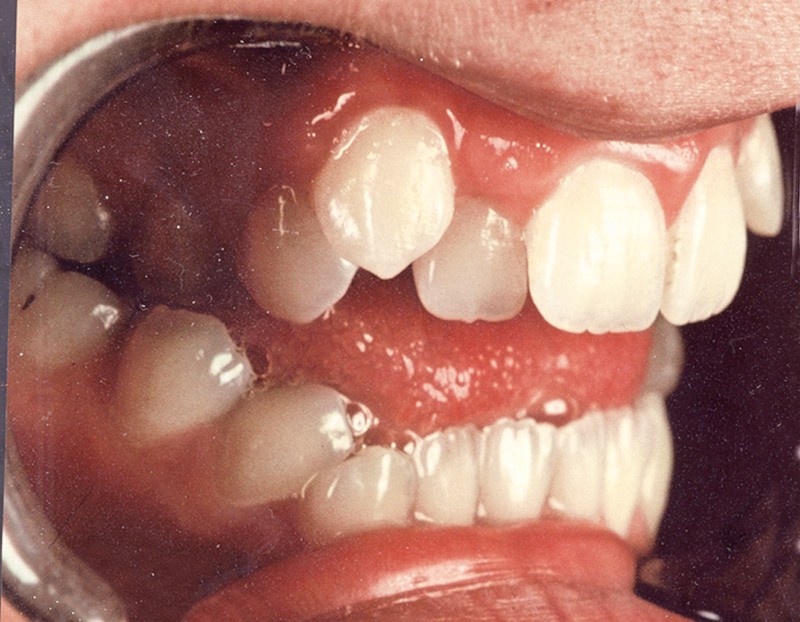

Sur le plan occlusal et dentaire, on observe une classe I molaire, une occlusion transversale en bout à bout à droite et inversée à gauche et une béance antérieure sévère s’étendant jusqu’aux molaires. Un encombrement est présent aux deux arcades avec des dystopies canines importantes (fig. 2).